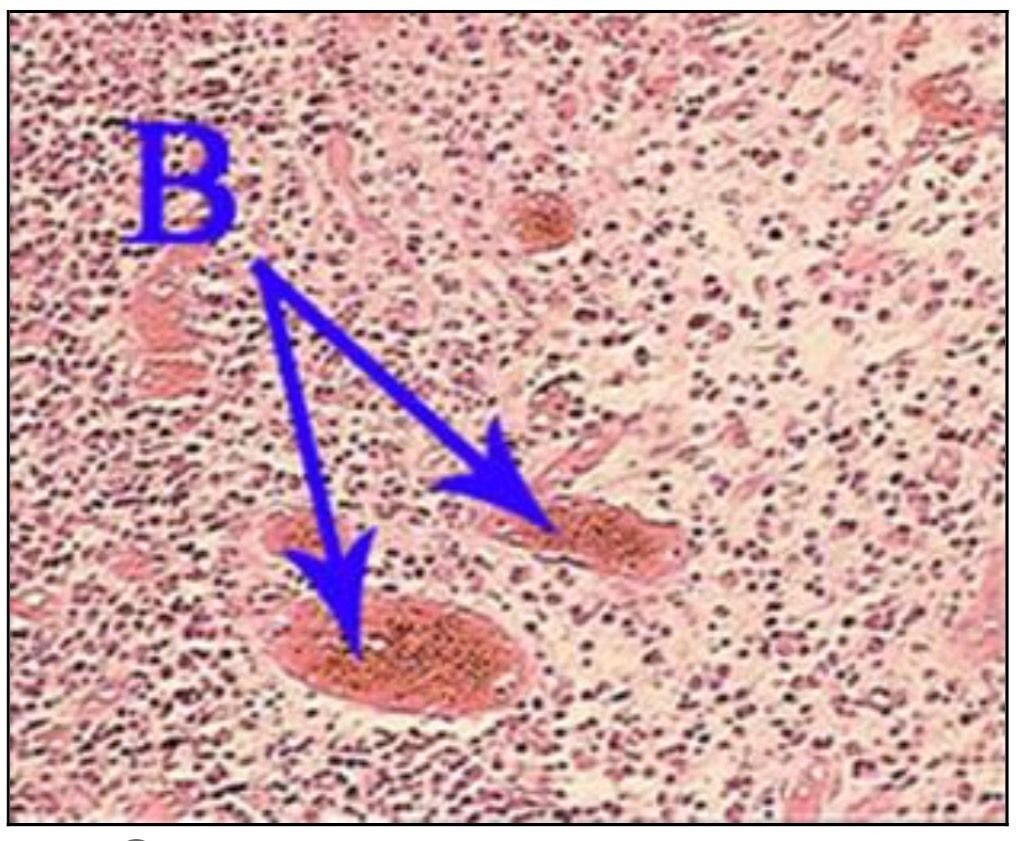

Question 16

Question

What is the correct answer at point A?

Answer

• - veine Centro lobulaire

• - travée hépatocytaire

• - dépôt amyloïde péricentrolobulaire

• - substance amyloïde intercellulaire

• - dépôt amyloïde dans l’espace porte

Question 17

What is the correct answer at point B?

Question 18

What is the correct answer at point C?